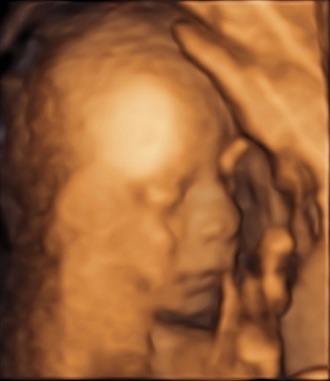

Das „kleine“ Geheimnis ist gelüftet - Tagebücher aus der Schwangerschaft von Martina aus Berlin